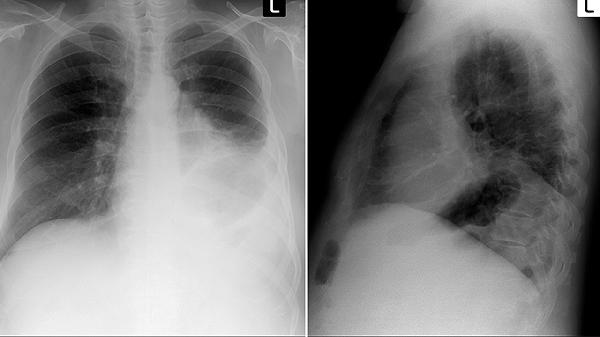

长期吸烟者、有肺癌家族史的人群、接触石棉等致癌物的职业人群,如果出现上述任何症状,建议尽快做低剂量螺旋CT检查。这是目前筛查早期肺癌最有效的手段,能发现小于1厘米的微小结节。